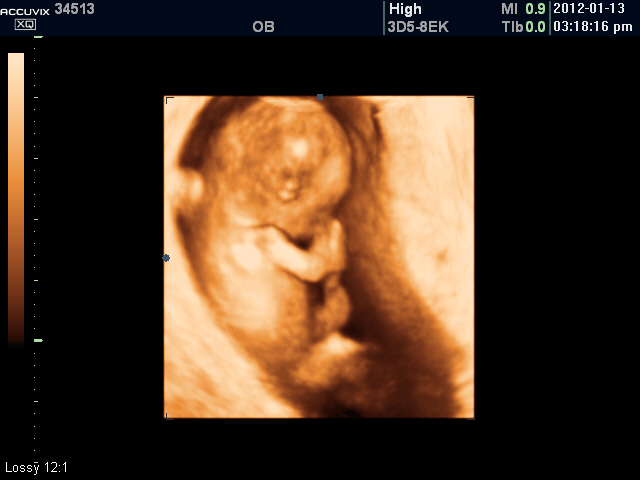

위 사진은 본원에서 찍은 임신 초음파로 12주 된 태아의 2차원 이미지와 입체 모습입니다.